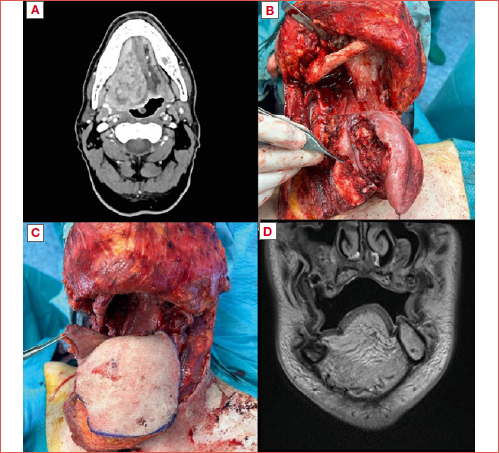

The indications to perform TGL rather than SG/TG with laryngeal preservation was related to tumour extension. According to the Ansarin et al. classification 19, in 23.9% of patients the BOT was bilaterally preserved (type IVa SG), in 32.9% only on one side (type IVb SG), and in 26.8% the BOT was bilaterally removed (type V TG). Laryngeal preservation was achieved in 56 (83.6%) patients, while the remaining 16.4% underwent TGL. Other surgical extensions included the tonsil or lateral wall of the oropharynx in 34 (50.7%) cases, buccal mucosa in 9 (13.4%), and alveolar crest mucosa in 14 (20.9%). Segmental and marginal mandibulectomy were performed in 8.9% (n = 6) and 23.9% (n = 16) of patients, respectively (Cover figure).